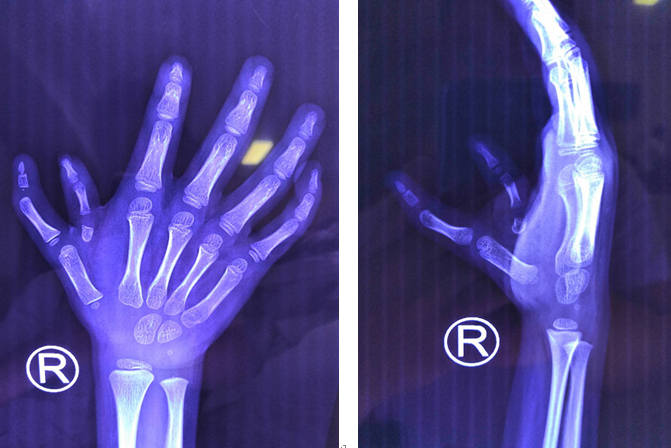

(術(shù)前術(shù)后對(duì)比圖)

(術(shù)前檢查)

正常情況下,人總共有10根手指頭,但浩浩卻不同,他天生就雙手畸形有12根手指:左手多指畸形,2歲時(shí)已經(jīng)在仁慈做了矯正;右手因?yàn)楸容^復(fù)雜,一直在等合適的機(jī)會(huì)。

浩浩的主治醫(yī)生,徐州仁慈醫(yī)院手外科朱輝主任介紹,“這個(gè)孩子右手比較特殊,兩根拇指,一個(gè)外形長(zhǎng)的好看沒(méi)有功能,一個(gè)功能比較好但沒(méi)有指甲。單純留哪一個(gè)都不完美,合并在一起,才能成一個(gè)較接近正常的手指。這既需要相當(dāng)?shù)募夹g(shù)做保證,也需要骨骼發(fā)育到一定程度才能做手術(shù)。”

(術(shù)后檢查)